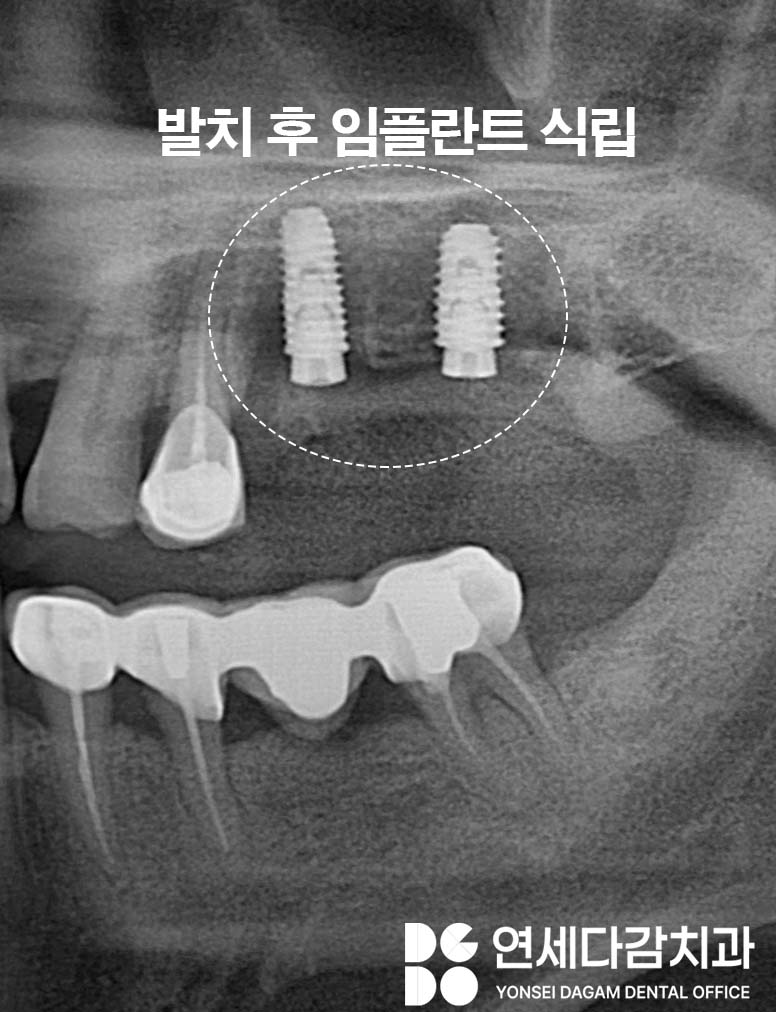

따라서 브릿지를 제거했을 때 지대치가

더 이상 기능하기 어려운 상태라면

발치 후 임플란트를 고려하게 됩니다.

골상태가 양호하다면

당일 발치와 동시에 임플란트를 식립하는

즉시 임플란트 방식을

적용할 때가 많습니다.

이 경우 빠른 회복을 유도할 수 있고

치료 기간을 단축되어

불편감도 빠르게 해소될 수 있습니다.